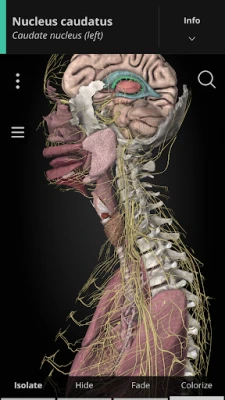

Using our cutting-edge 3D model, which is one of the most detailed in the world, ANATOMYKA allows you to get up close with human anatomy in all its breathtaking complexity on more than 13,000 anatomical structures with more than 500 pages of medical descriptions. Now in English, Spanish, Italian, Polish, Russian, Czech, Slovak and Hungarian localization.

In the ANATOMYKA app, each anatomical system, organ and part is accompanied by detailed information about its structure, hierarchy, regions, including information about organs, clinical notes, related organs (vascular supply, innervation, syntopy) and a general description.

Color-coded organs allow users to view high-resolution anatomical structures supplemented by informative descriptions from a comprehensive textbook ‘Memorix Anatomy’. These are arranged into a proper anatomical hierarchy, meaning learning is structured and easy to understand.

View blood supply, innervation and syntopy for most organs

- User-friendly interface: Zoom, rotate, scale, colorize, isolate, select, hide, and fade all anatomical structures